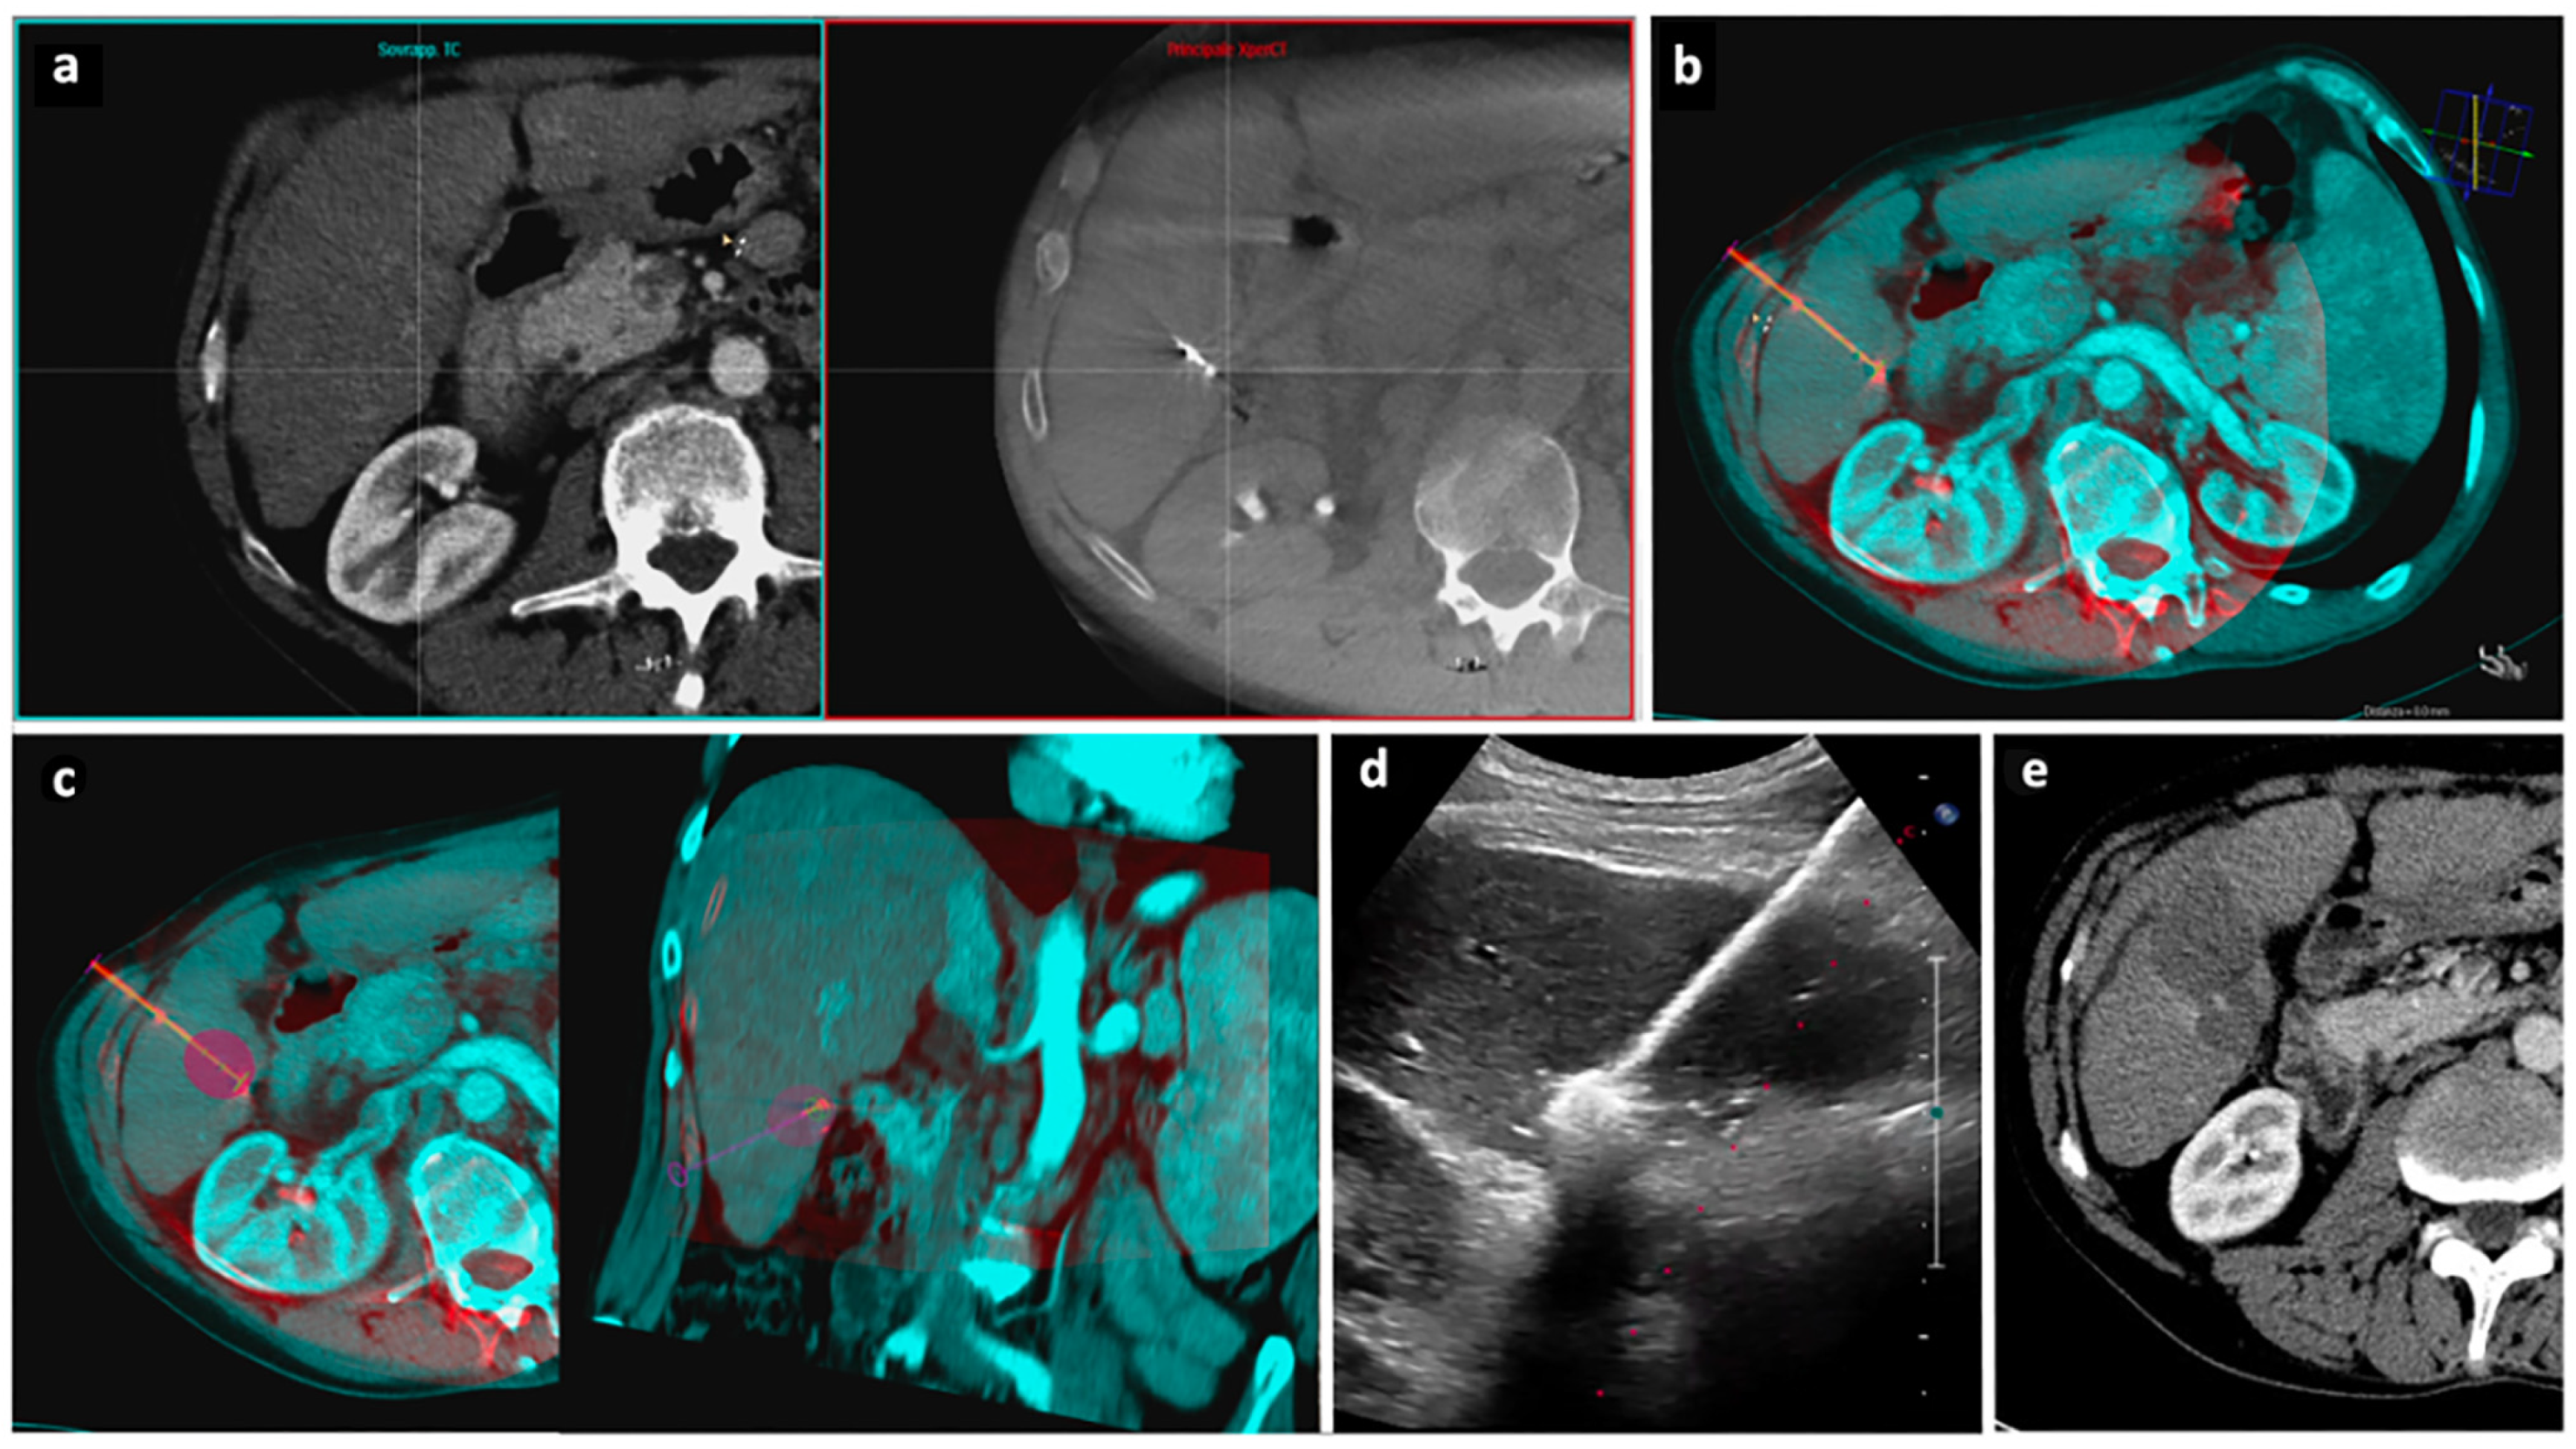

Figure 4. “Double fusion” technique—Part 2. After the MWA antenna is placed into the tumor (Figure 3), an unenhanced CBCT is acquired and CBCT fusion imaging is performed. (a) The manual registration process begins with the side-by-side visualization on the workstation of preprocedural CT images on the left and intraprocedural CBCT images on the right. (b) CT images are superimposed to CBCT images to assess the spatial relationship between the tumor and the MWA antenna; a virtual antenna is placed exactly over the real one. (c) The predicted ablation volume is displayed as a purple area at the tip of the virtual antenna based on the selected ablation power and time, according to the MWA device manufacturer data; the predicted ablation volume is here assessed on the axial (left) and coronal (right) planes. (d) If the antenna position is judged satisfactory by CBCT fusion imaging, ablation is carried out under US guidance. (e) Follow-up axial CT images acquired 1 month after procedure demonstrate complete response. Abbreviations—CBCT: cone beam computed tomography; CT: computed tomography; MWA: microwave ablation; US: ultrasound.